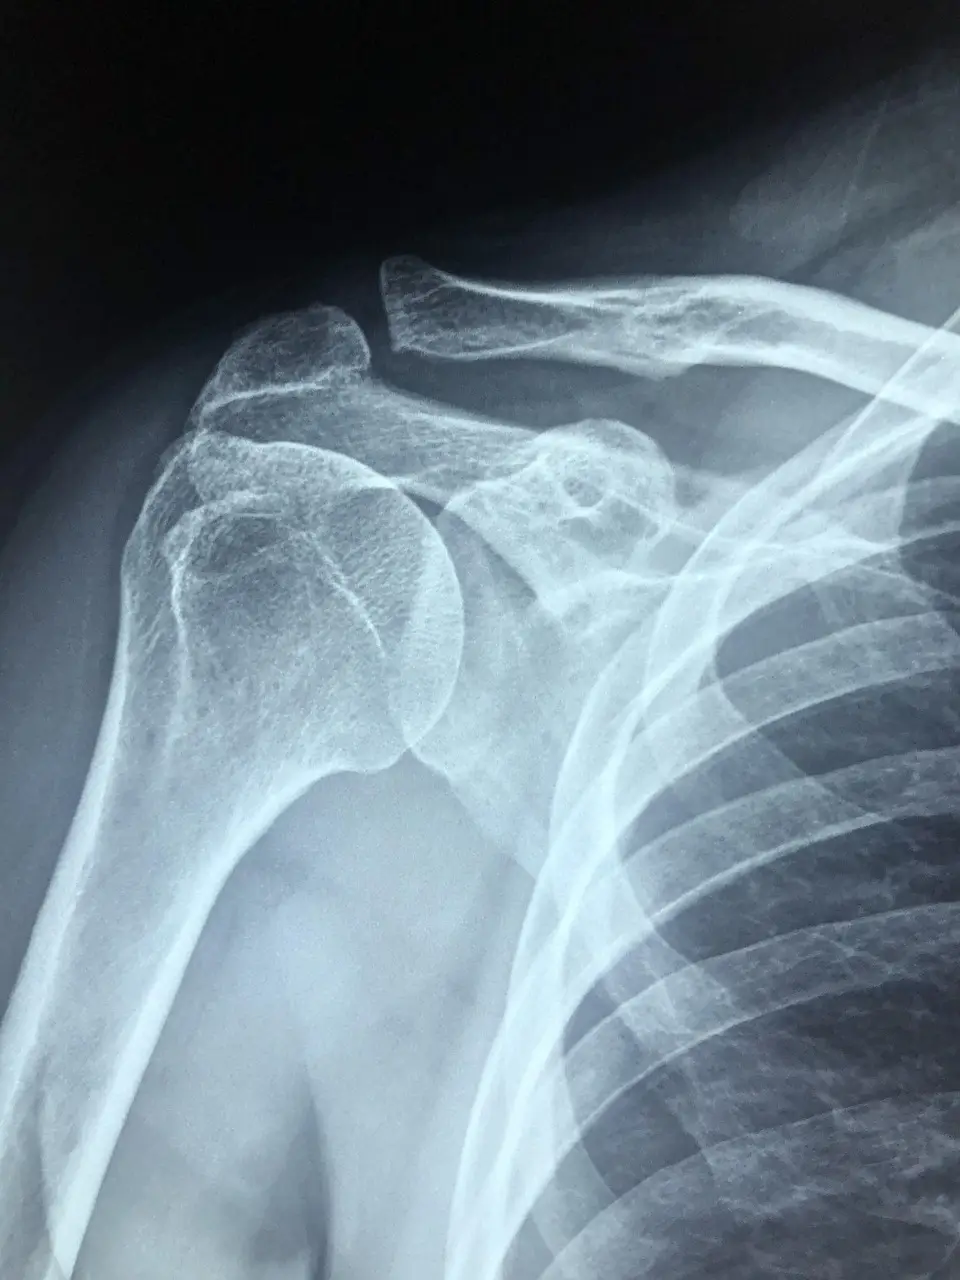

어깨석회화건염은 어깨 관절을 움직이는 힘줄(특히 회전근개)에 칼슘 침착이 생겨 염증과 통증을 유발하는 질환입니다. 처음에는 뻐근한 느낌만 들지만, 점차